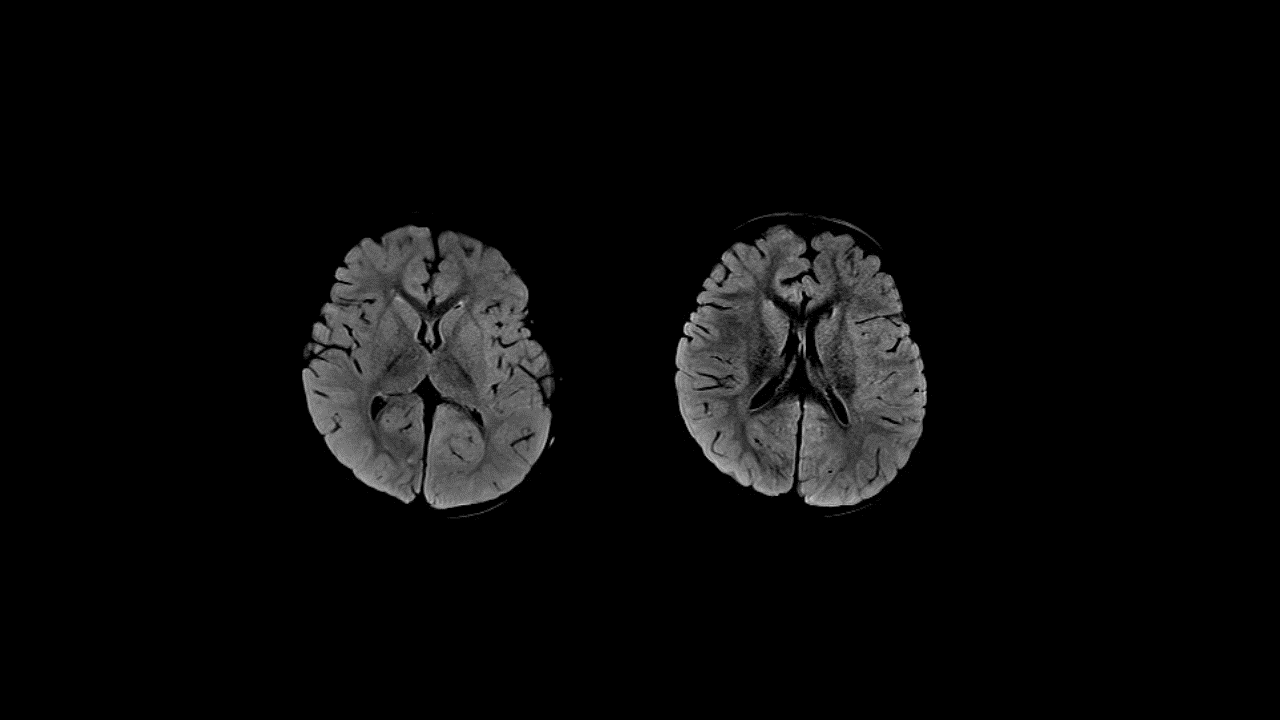

Symmetric areas of Restricted Diffusion in the bilateral temporal and parieto-occipital subcortical and periventricular white matter and in the bilateral frontal subcortical white matter. The white matter depicts a “bright tree appearance” which represents high-signal intensity on DWI B1000 in the subcortical white matter, akin to tree branches.

Areas of Restricted Diffusion are also seen in the leftthalamus, caudate nuclei bilaterally, dorsal pons, inferior cerebellar cortex in the paramedian location and in the superior vermis.

Subtle thickening of the cortex in the bilateral parieto-occipital regions with mild blurring of gray-white matter interface in these regions.

Imaging features suggest diffuse type Acute Leukoencephalopathy with Restricted Diffusion - ALERD